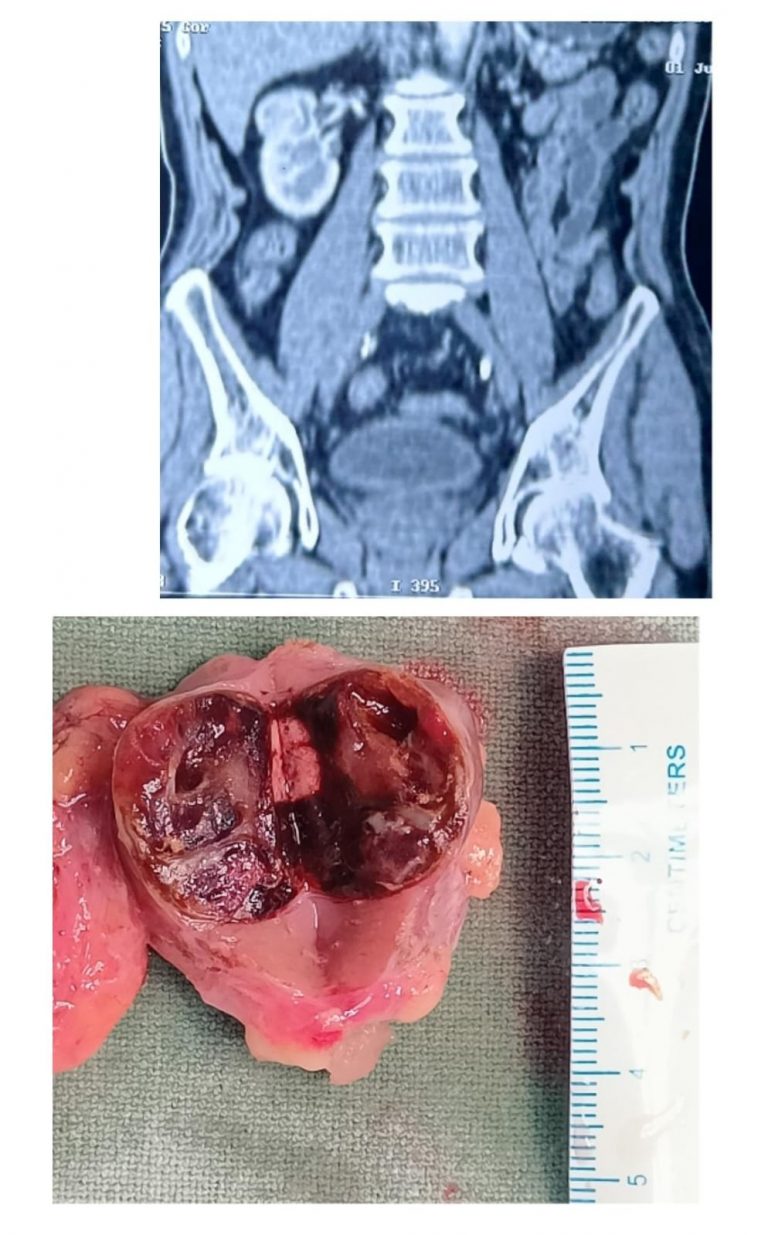

The patient, with diabetes, high blood pressure and chronic kidney disease (CKD), was diagnosed with a 4 cm x 4 cm tumour on his left kidney. He was given the option of laparoscopic partial nephrectomy as he had multiple comorbidities and CKD, and removing the cancer-only part with intact kidney was best for him.

Dr Mishra and his team performed the complex procedure of partial nephrectomy by laparoscopic method, or keyhole surgery, successfully.